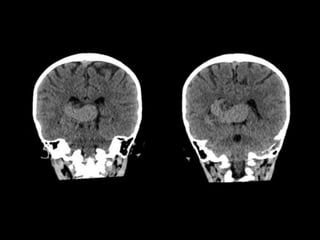

TC SIMPLE DE CRANEO

08/06/2023

CORTE

AXIAL

CORONAL

SAGITAL

VOLUMEN: 25,1 CC

Lesión ocupante de espacio extraaxial

supratentorial a nivel de cisterna cuadrigeminal.

CONCLUSIONES: